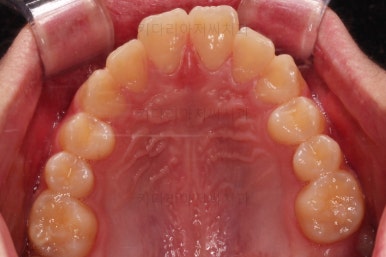

초진 때의 입 안의 모습이에요.

집 근처 치과에서 어금니가 나와야되는데 보이지 않는다는 말씀을 듣고 찾아오셨어요.

치열이 조금 삐뚤긴 하지만 교정치료는 크게 관심이 없었던 환자분이었어요.

밥 먹는 것도 크게 불편함이 없었고요.